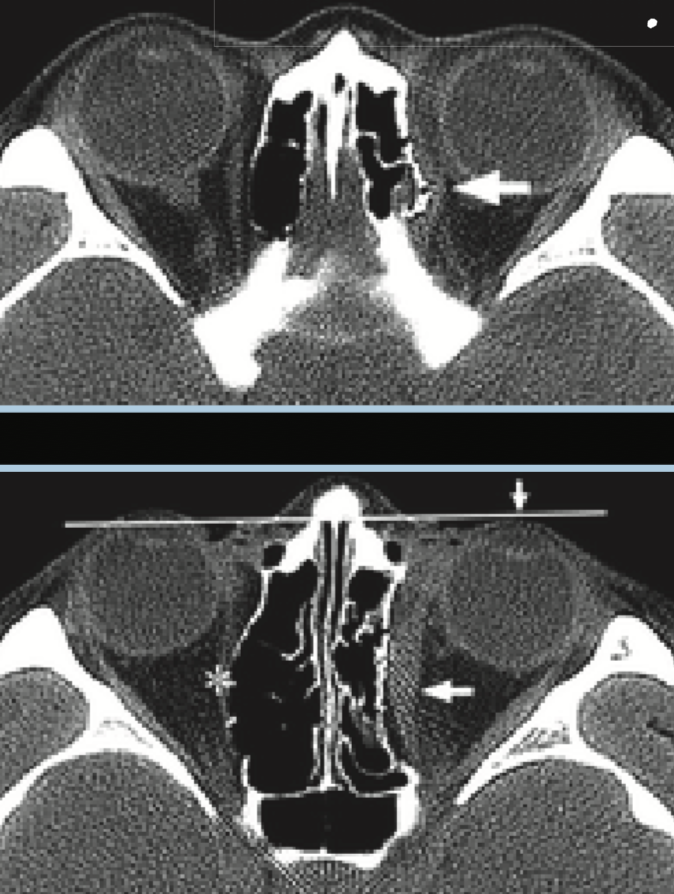

ORBITAL FRACTURES?

Orbital Apex fragments can lead to optic nerve damage

SKB FRACTURES - Signs of each skull base fractures?

…